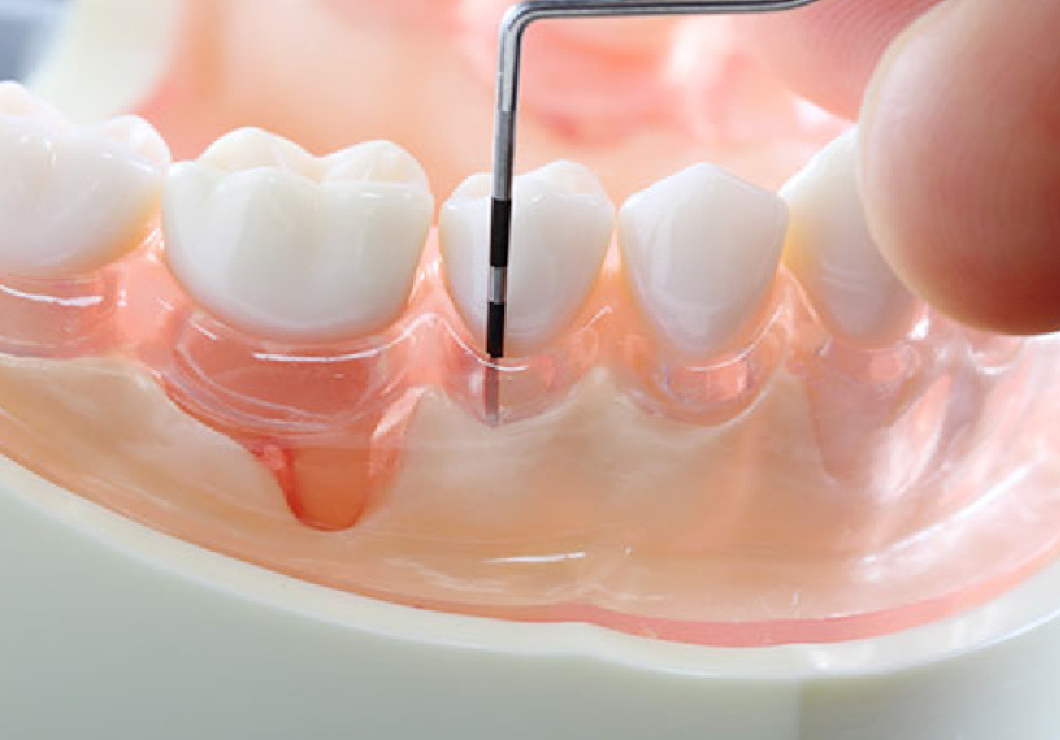

根管治療とは、歯の根の中にある根管を対象に行う治療です。

むし歯が進行すると、細菌が根管まで達して炎症を引き起こし、ズキズキとした強い痛みが出ることがあります。

このようなケースでは、細菌に感染した根管内の神経を丁寧に取り除いた上で、根管の中を消毒・殺菌し、薬剤を充填して密閉する処置が必要です。

かつては抜歯しか選択肢がなかったような状態でも、現在は根管治療によって、歯を残すことができる可能性が広がっています。

精密な根管治療を可能にするマイクロスコープ

患者さまにより精度の高い治療を受けていただけるように、当院ではマイクロスコープを導入しています。

根管は枝分かれしつつ曲がりくねっているため、肉眼で内部を確認するのは困難です。マイクロスコープを使うことで最大40倍の拡大視野で、細部まできちんと見ながら治療を進めることができます。

また、肉眼では気づきにくい歯の表面にある小さなひび割れや段差なども、発見することが可能になります。